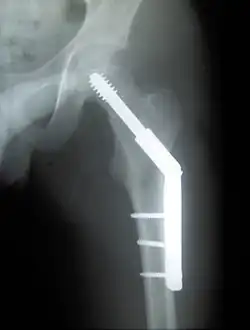

Closed reduction may not be satisfactory and open reduction then becomes necessary.[43] The use of open reduction has been reported as 8-13% among pertrochanteric fractures, and 52% among intertrochanteric fractures.[44] Both intertrochanteric and pertrochanteric fractures may be treated by a dynamic hip screw and plate, or an intramedullary rod.[43]

The fracture typically takes 3–6 months to heal. As it is only common in elderly, removal of the dynamic hip screw is usually not recommended to avoid unnecessary risk of second operation and the increased risk of re-fracture after implant removal. The most common cause for hip fractures in the elderly is osteoporosis; if this is the case, treatment of the osteoporosis can well reduce the risk of further fracture. Only young patients tend to consider having it removed; the implant may function as a stress riser, increasing the risk of a break if another accident occurs.